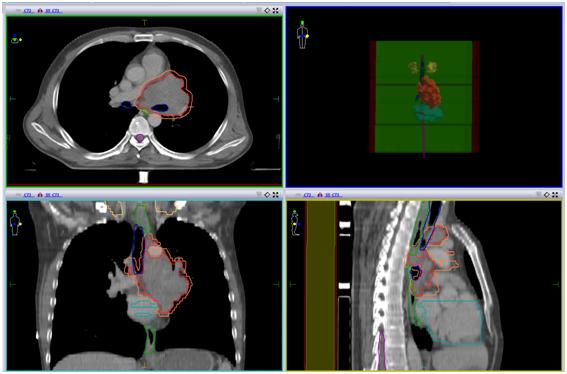

患者急诊来我院,具体治疗计划如下:

• (肺及纵隔病灶)iGTV1/GTV1/CTV1/70Gy/60Gy/50Gy/20F;

• (锁骨上病灶)GTV2/CTV2/60Gy/50Gy/20F。